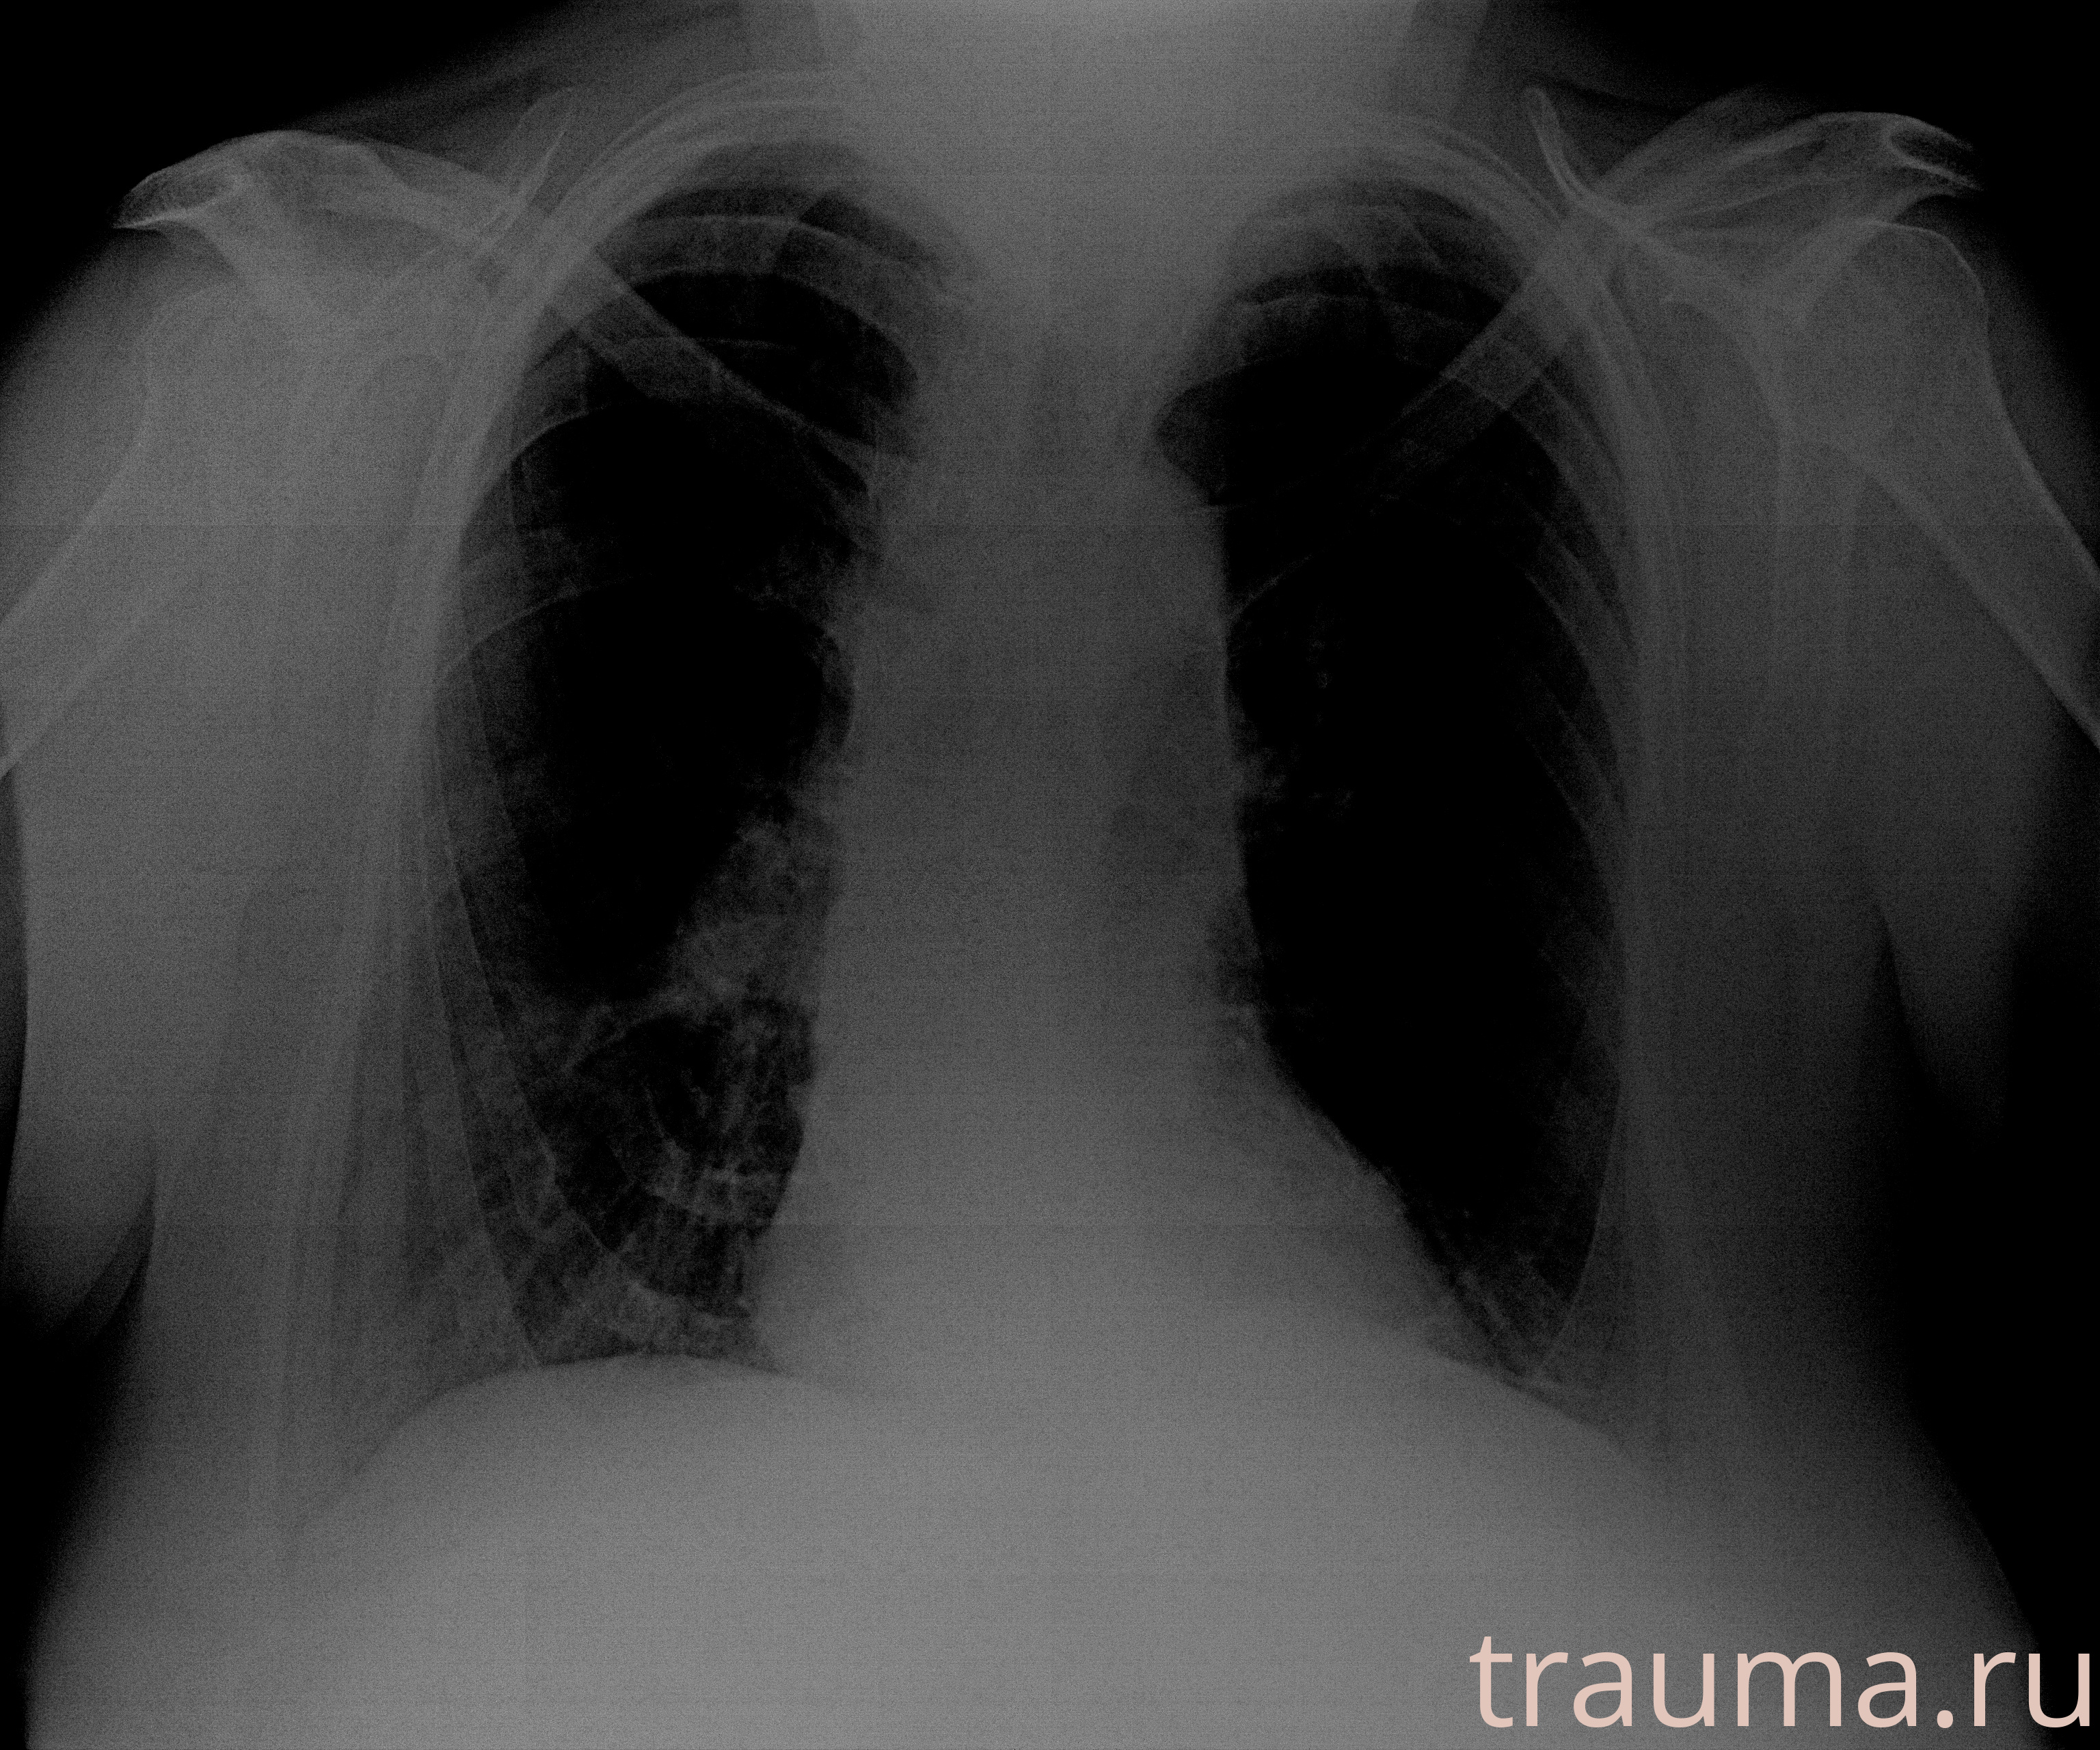

при переломе шейки бедра и пневмонии от компании МосРентген Центр - партнера Института имени Склифосовского

Рентген на дому: по вашему адресу приезжает врач-рентгенолог, травматолог-ортопед с мобильным рентгеновским аппаратом, проводит диагностику травмы или заболевания, делает необходимые рентгенограммы, дает рекомендации по дальнейшему лечению. Получить качественные снимки в домашних условиях возможно благодаря уникальной методике, разработанной МосРентген Центром для института  Склифосовского